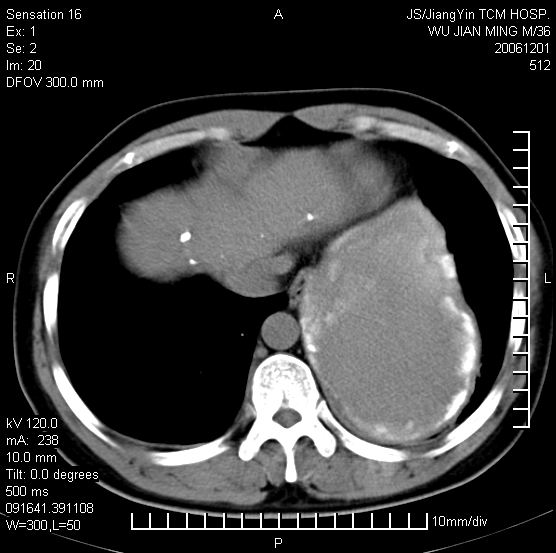

以下是引用dyqct在2006-12-1 21:17:00的发言:[br]左心缘旁及后肋膈窦区见巨大椭圆形混杂密度肿块,周围见大小不等斑片状钙化,内部无强化,周围包膜轻度强化,心脏明显受压变形,即明显占位效应,肿块广基与心包、膈相连。肝、脾内、肝门见多数小结节状钙化影。[br]考虑:1、左心缘旁及后肋膈窦区慢性包裹性胸膜炎(结核性);[br] 2、肝、脾及肝门淋巴结核已钙化。[br]

以下是引用zrs在2006-12-2 17:28:00的发言:[br]肺内、肝脾内虽有钙化,但不支持结核性胸胸膜炎包裹,而支持寄生虫感染![br][br]

以下是引用zyx168在2006-12-2 10:10:00的发言:[br][br]肝脾肺内多发钙化灶